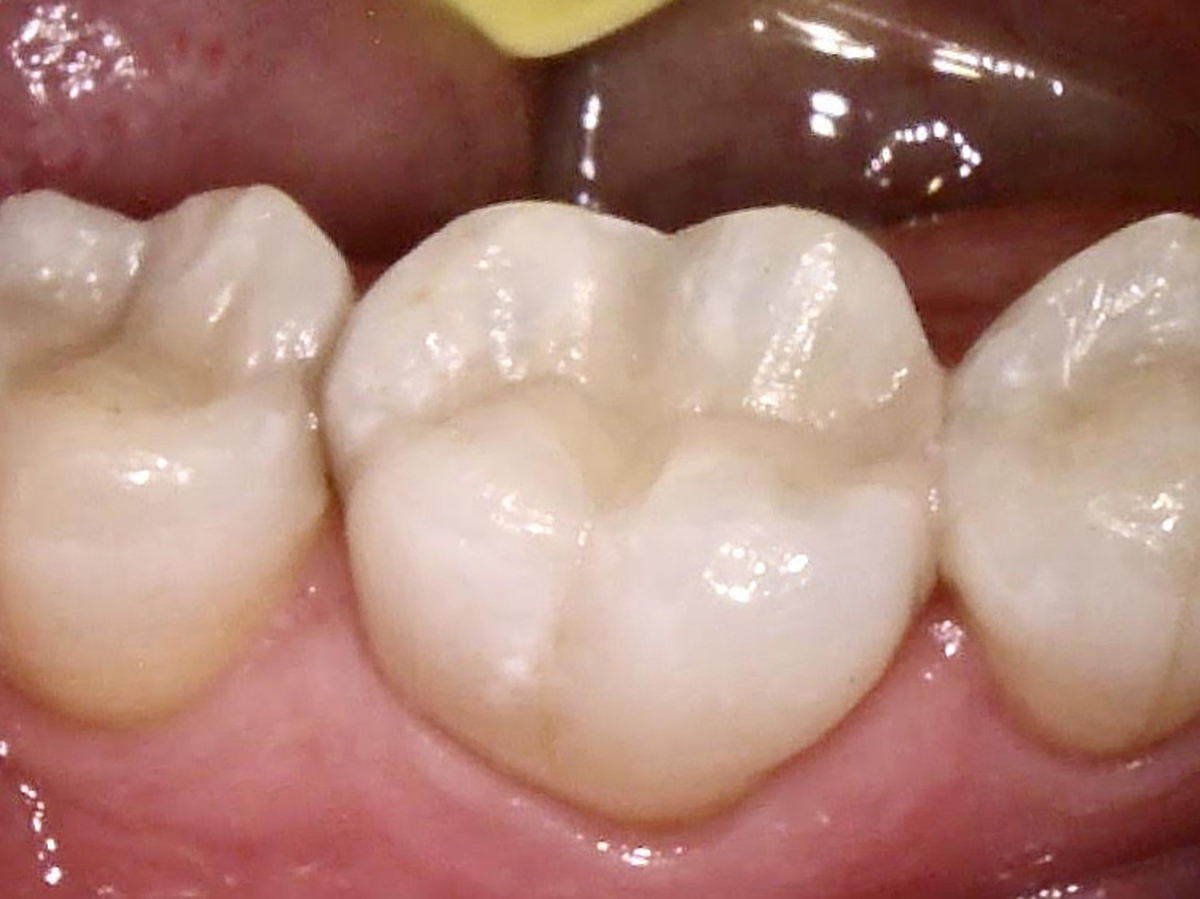

Fig 6. Tooth No. 30, postoperative.

Figure 6

Fig 8. Six-month recall image of restoration.

Figure 8